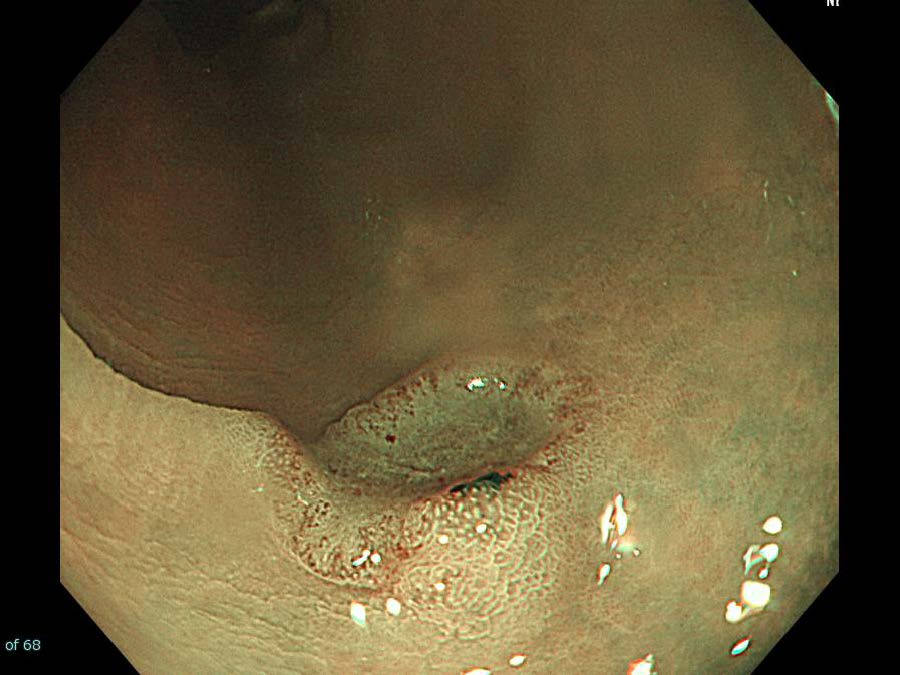

消化管Mapping~大腸~ 2021.10.27

消化管Mapping~大腸~

消化器内科

内視鏡検査・治療

消化管Mapping